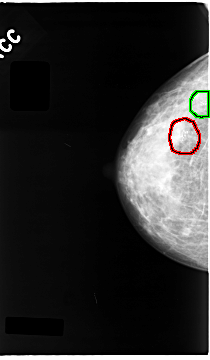

C_0063_1.RIGHT_CC

FILE: C_0063_1.RIGHT_CC.OVERLAY

TOTAL_ABNORMALITIES 2

ABNORMALITY 1

LESION_TYPE CALCIFICATION TYPE PLEOMORPHIC DISTRIBUTION CLUSTERED

ASSESSMENT 5

SUBTLETY 5

PATHOLOGY MALIGNANT

TOTAL_OUTLINES 1

BOUNDARY

ABNORMALITY 2